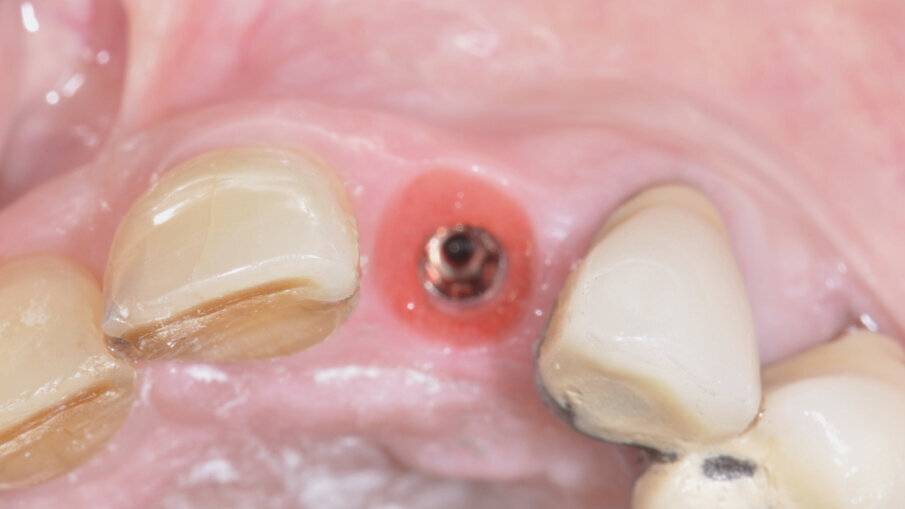

A 7 giorni è stato eseguito un controllo per verificare lo stato dei tessuti gengivali e continuare a motivare la paziente riguardo all’esclusione dai carichi masticatori (Fig. 9). A 90 giorni è stato rimosso il provvisorio per procedere al restauro ceramico. Nonostante la superficie SLActive preveda un accorciamento dei tempi di integrazione, è stato deciso un tempo di attesa convenzionale per accertarsi della stabilità dei tessuti molli perimplantari (Figg. 10-12). È stato eseguito un workflow digitale a partire dall’impronta ottica, fino alla realizzazione di un restauro in Zirconia precolorata e stratificata vestibolare (Dental Direkt 1200 e Creation ZI-CT) su base titanio (Figg. 13, 14). Il restauro è stato consegnato mediante avvitamento a controllo di torque secondo le indicazioni della casa produttrice (Figg. 15, 16).

Fig. 10_Aspetto clinico a 90 giorni.

Fig. 11_Condizionamento dei tessuti molli.